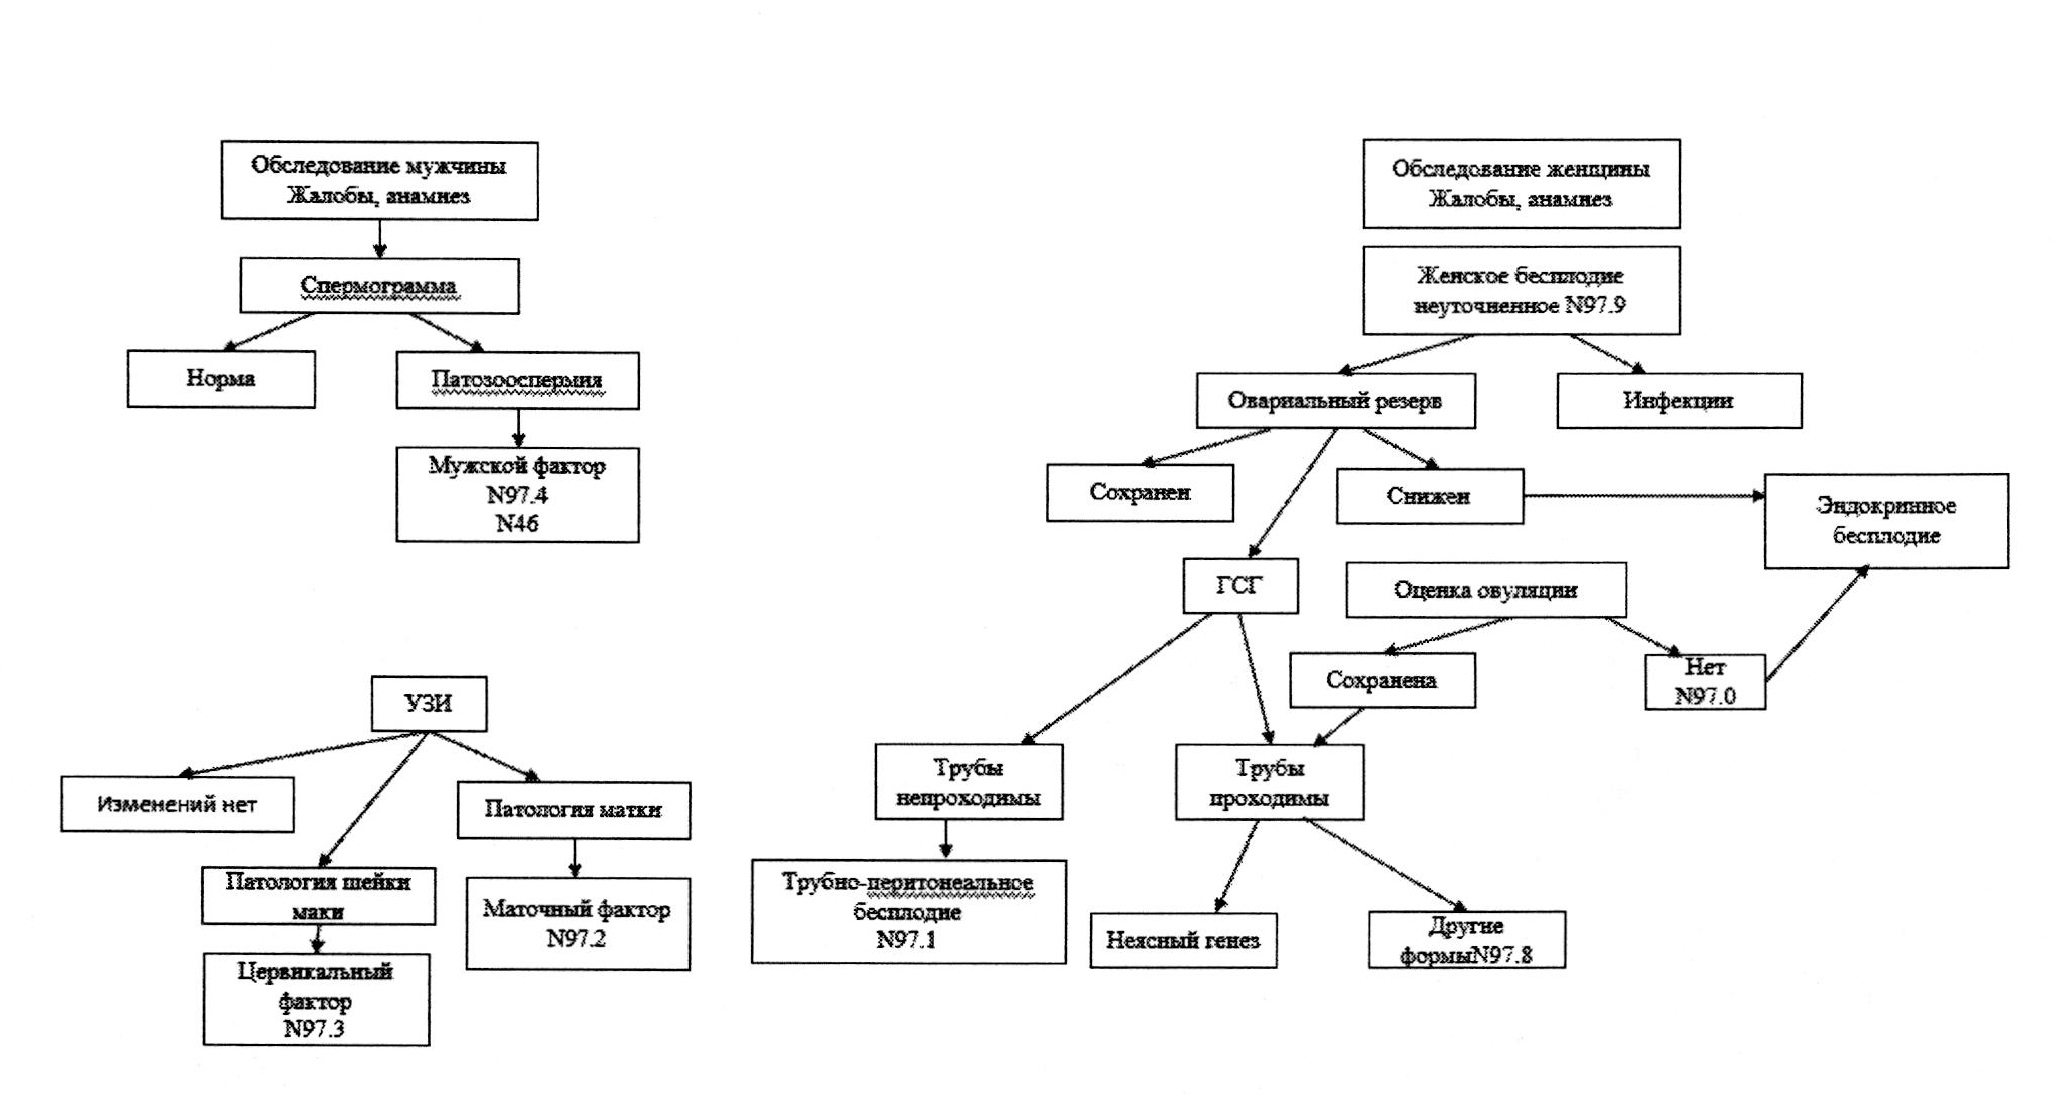

2. Женское бесплодие

В соответствии с рекомендациями ВОЗ и требованиями Министерства здравоохранения РФ, МКБ-10 является единственным нормативным документом формулировки и учета диагнозов в системе здравоохранения на территории страны.

N97. Женское бесплодие (включены: неспособность забеременеть, стерильность женская); (исключены: относительное бесплодие).

N97.0. Женское бесплодие, связанное с отсутствием овуляции.

N97.1.Женское бесплодие трубного происхождения (связанное с врожденной аномалией маточных труб или трубной непроходимостью).

N97.2.Женское бесплодие маточного происхождения (связанное с врожденной аномалией матки, дефектами имплантации яйцеклетки).

N97.3.Женское бесплодие цервикального происхождения.

N97.4.Женское бесплодие, связанное с мужскими факторами.

N97.8.Другие формы женского бесплодия.

N97.9 Женское бесплодие неуточненное.

Мужское бесплодие закодировано единственным шифром N46 - Мужское бесплодие (азооспермия, олигозооспермия).

2.1. Диагностика

2.1.1. Обследование женщины

Инструментальная диагностика

- УЗИ малого таза рекомендовано всем женщинам с бесплодием для определения размеров матки и яичников, диагностики новообразований матки и ее придатков, аномалий развития внутренних половых органов, патологических процессов в эндометрии (полипы, гиперплазия, хронический эндометрит), толщины эндометрия, а также определения КАФ (срок годности исследования - 6 месяцев).

- Оценка проходимости маточных труб проводится с помощью гистеросальпингографии (ГСГ) и/или соногистеросальпингографии, по показаниям - лапароскопии (срок годности исследования - 1 год). С помощью ГСГ и соногистеросальпингографии также определяют размер и форму полости матки, аномалии развития матки, приобретенные аномалии полости матки (субмукозная миома, полипы, внутриматочные синехии).

2.1.2. Обследование мужчины

Проводится исследование эякулята мужа (партнера) (срок годности исследования - 6 месяцев).